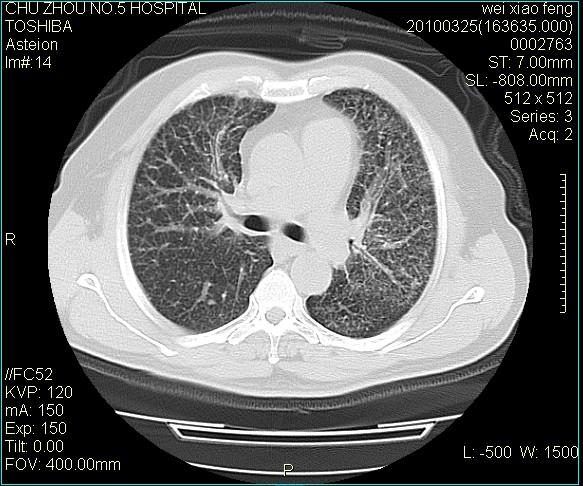

男,60岁,反复咳、痰、喘3月,加重3天。

双肺间质性改变。

考虑双肺血型潘散肺结核/

间质性肺炎伴间质纤维化!不排除伴有职业病!

急性血型潘散肺结核。

双肺间质纤维化,双肺血型潘散肺结核。

考虑间质性肺炎伴间质纤维化。

右肺中叶结节影为原发灶,考虑右肺中叶周围型肺癌并淋巴道转移